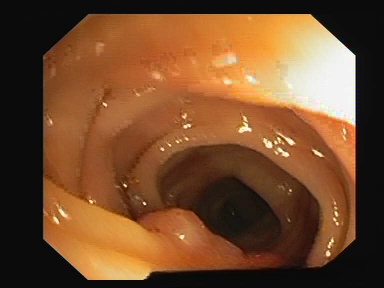

1、ClinicDB : 这是一个开放的数据集,致力于提供高质量的结肠镜图像以及相应的结肠息肉标注. 该数据集旨在促进计算机辅助诊断(CAD)系统的研发,从而在临床环境中提高结肠息肉检测与分类的效率. 数据集中包含大量高清晰度的医学影像,并结合多模态标注信息,为相关领域的研究提供丰富的学习素材. 通过系统化的数据积累,ClinicDB不仅能够显著提升诊断准确性,还能为临床实践提供科学依据.

处理好后的COCO格式的数据集图像的总数为612张,类型标签为病灶区域。